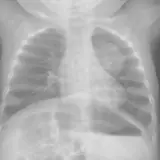

Over 2,100 interactive radiology cases, curated by radiologists for your level of training. Scroll, window, and view cases full screen — just like on PACS. Click linked findings in each writeup to jump straight to them on the image. Cases include sample reports, a focused discussion section, original illustrations, and videos.

Casos totalmente interactivos con las herramientas que esperaría de un PACS: scroll, ventana, zoom, pan, mediciones, ROI y modo de pantalla completa.

• Anotaciones enlazadas

Anotaciones extensas resaltan los hallazgos clave directamente sobre los casos. Haga clic en los hallazgos enlazados dentro de la descripción del caso para saltar a su ubicación exacta en el estudio.

Casos Interactivos

Desplace, arrastre, ajuste ventana y amplíe como en una estación PACS de trabajo

Aprenda con eficiencia gracias a hallazgos de imagen anotados e ilustraciones